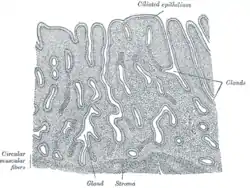

The uterus has three layers, which together form the uterine wall. From innermost to outermost, these layers are the endometrium, myometrium, and perimetrium.[5]

The endometrium is the inner epithelial layer, along with its mucous membrane, of the mammalian uterus. It has a basal layer and a functional layer; the functional layer thickens and then is sloughed during the menstrual cycle or estrous cycle. During pregnancy, the uterine glands and blood vessels in the endometrium further increase in size and number and form the decidua. Vascular spaces fuse and become interconnected, forming the placenta, which supplies oxygen and nutrition to the embryo and fetus.[6][7]

The myometrium of the uterus mostly consists of smooth muscle. The innermost layer of myometrium is known as the junctional zone, which becomes thickened in adenomyosis.[8]

The perimetrium is a serous layer of visceral peritoneum. It covers the outer surface of the uterus.[9]

Vertical section of mucous membrane of human uterus

Vertical section of mucous membrane of human uterus